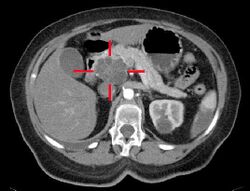

Medical imaging techniques, such as computed tomography (CT scan) and endoscopic ultrasound (EUS) are used both to confirm the diagnosis and to help decide whether the tumor can be surgically removed (its "resectability").[12] On contrast CT scan, pancreatic cancer typically shows a gradually increasing radiocontrast uptake, rather than a fast washout as seen in a normal pancreas or a delayed washout as seen in chronic pancreatitis.[56] Magnetic resonance imaging and positron emission tomography may also be used,[2] and magnetic resonance cholangiopancreatography may be useful in some cases.[32] Abdominal ultrasound is less sensitive and will miss small tumors, but can identify cancers that have spread to the liver and build-up of fluid in the peritoneal cavity (ascites).[12] It may be used for a quick and cheap first examination before other techniques.[57]